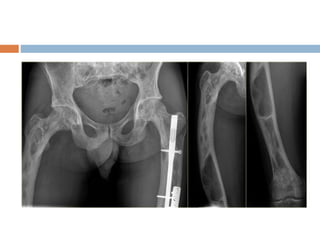

Fibrous dysplasia

 Developmental disorder in which areas of

trabecular bone are replaced by cellular

fibrous tissue containing flecks of osteoid and

woven bone.

 May affect one bone (mono-ostotic), one limb

(monomelic) or many bones (polyostotic)

 Sites– proximal femur, tibia, humerus, ribs and

cranio-facial bones

Clinical features

 Small single lesion asymptomatic

 Large mono-ostotic lesions– pain or

pathological fracture

 Polyostotic disease– pain, limp, bony

enlargement, deformity or pathological fracture

 Albright syndrome = fibrous dysplasia + cafe-

au-lait spots + precocious puberty in girls

 Malignant transformation– 0.5% in mono-

ostotic lesion and upto 5% in Albright

syndrome

Diagnosis

 X-ray

 Radiolucent cystic areas in the metaphysis or

shaft

 The lucent areas have a hazy or ground glass

appearance (due to fibrous tissue)

 Weight bearing bone may be bent –

shepherd’s crook deformity of proximal femur